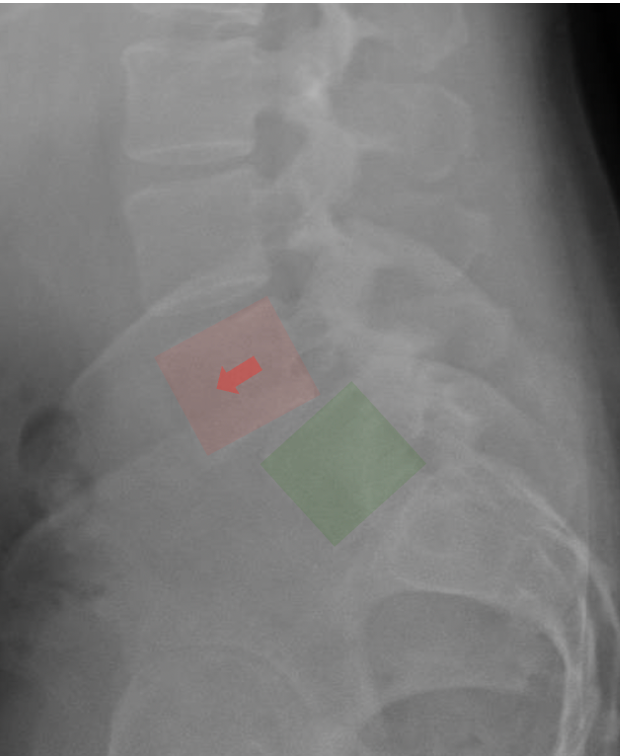

X-ray image of the lower spine showing a highlighted area with an arrow, with marked regions in red and green.

Comparison of two spinal X-rays, one with medical implants and markers highlighting features.